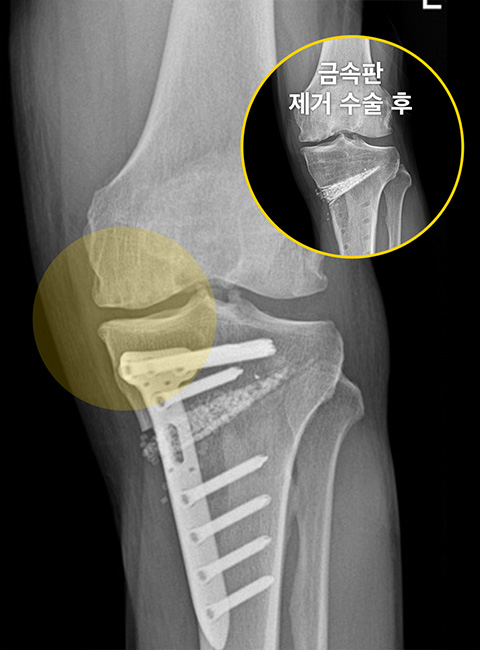

-

Before

무릎 안쪽 연골 간격이 좁아져 통증을 유발하는 상태

After

하중을 무릎 바깥쪽으로 분산시켜 좁아져 있던 무릎 안쪽 간격이 넓어짐 (금속판 제거 후 삽입한 인공뼈도 완전히 유합된 상태)